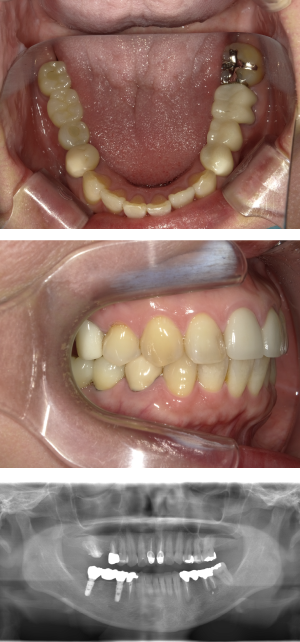

30代 女性 奥歯 インプラント

| 年代・性別 | 30代・女性 |

| 治療回数 | 10回(術前治療・検査除く) |

| 治療期間 | 約1年 |

| 料金 | ¥410,300(税込)※別途検査料 |

失った歯を補うために、インプラント治療は優れた治療方法です。 しかし、全ての人にインプラント治療が優れている治療ではありません。 |

| 副作用 | 術後に腫れ・痛みが出る可能性がある。 |